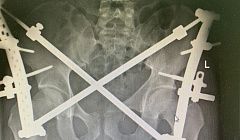

В Улан-Удэ врачи поставили на ноги мужчину, пострадавшего в страшном ДТП

Тогда вероятность летального исхода составляла 84%.